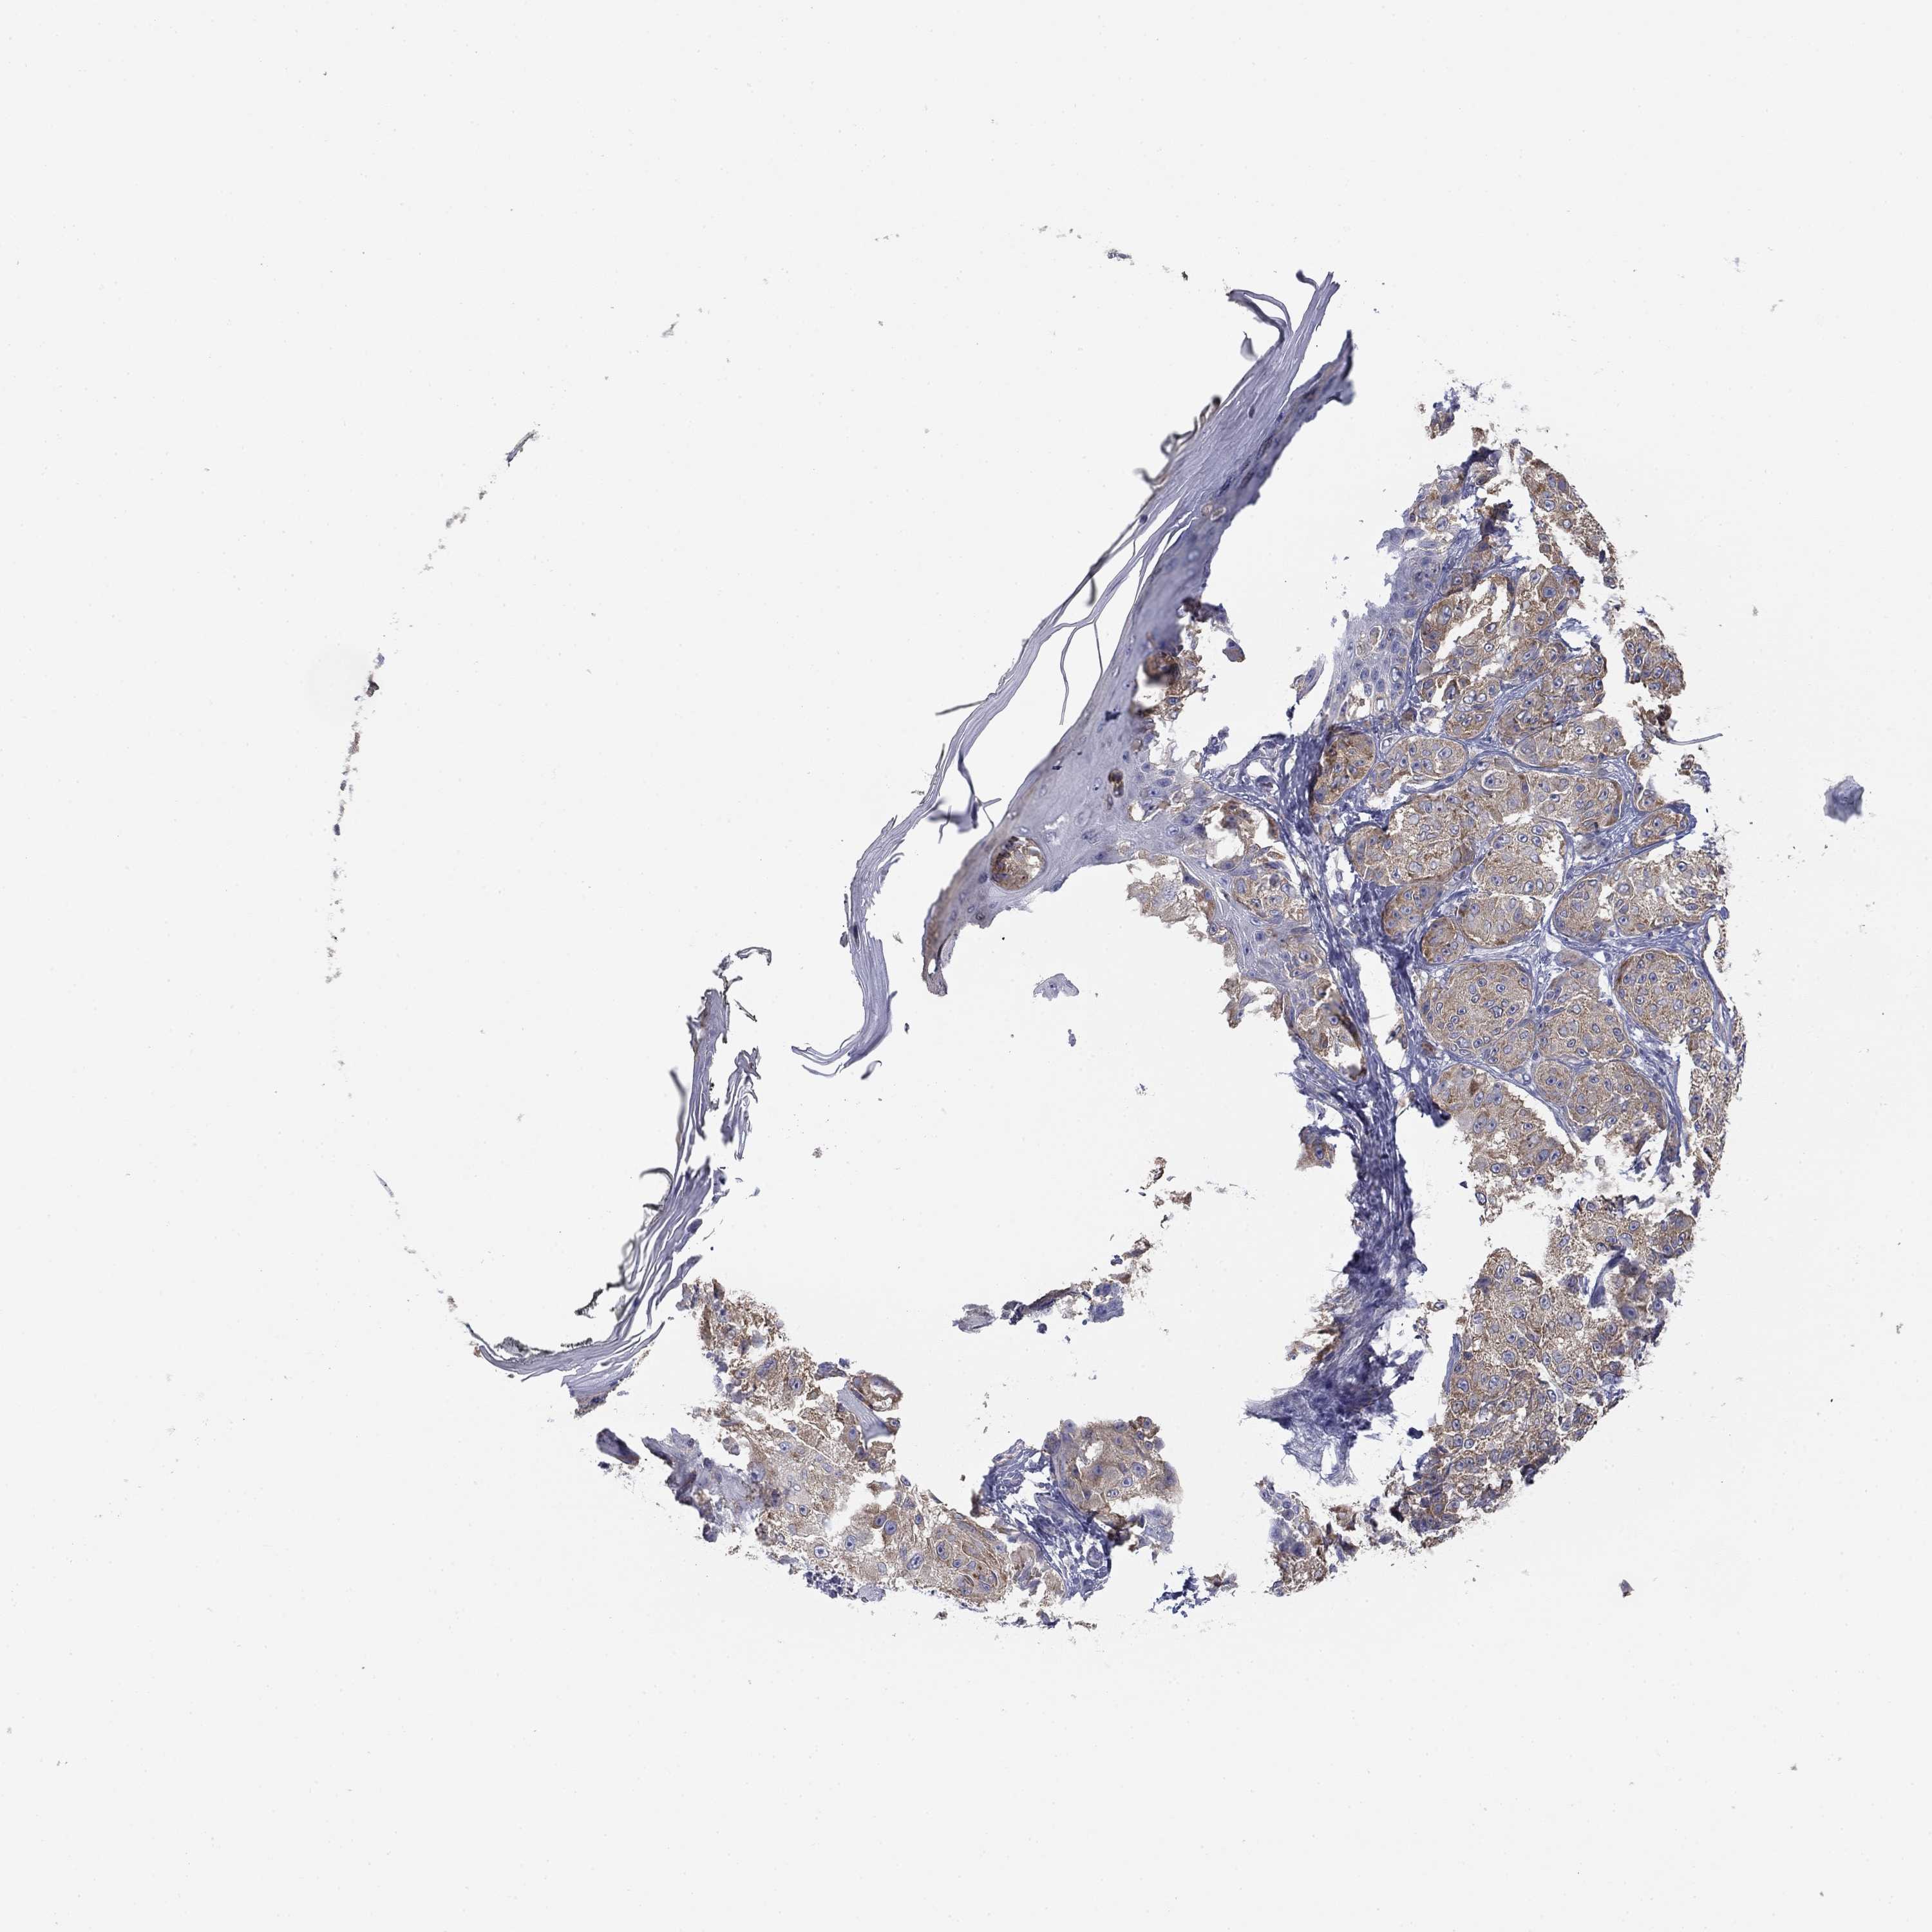

MELANOMA - Protein expressioni

A mouse-over function shows sample information and annotation data. Click on an image to view it in a full screen mode. Samples can be filtered based on level of antibody staining by selecting one or several of the following categories: high, medium, low and not detected. The assay and annotation is described here.

Note that samples used for immunohistochemistry by the Human Protein Atlas do not correspond to samples in the TCGA dataset.

Antibody stainingi

Antibody staining in the annotated cell types in the current human tissue is reported as not detected, low, medium, or high, based on conventional immunohistochemistry profiling in selected tissues. This score is based on the combination of the staining intensity and fraction of stained cells.

Each image is clickable and will lead to virtual microscopy that enables deeper exploration of all samples and also displays staining intensity scores, fraction scores and subcellular localization as well as patient and tissue information for each sample.

Antibody HPA003548

Antibody CAB017633

Staining

High

Medium

Low

Not detected

Intensity

Strong

Moderate

Weak

Negative

Quantity

>75%

75%-25%

<25%

None

Location

Nuclear

Cytoplasmic/membranous

Cytoplasmic/membranous,nuclear

Malignant melanoma, NOS

Malignant melanoma, Metastatic site